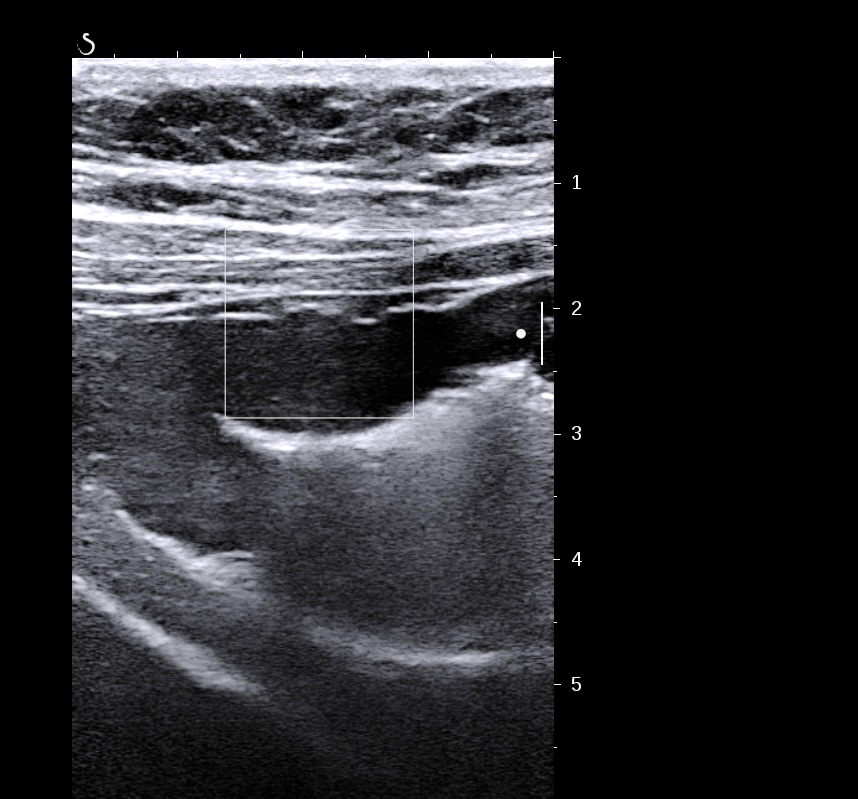

Exemple de paroi de 5 mm avec début de la disparition de la structure en couches (le contraste entre la muqueuse et la sous muqueuse est moins visible)

L'épaississement est encore plus important (8 mm), la surfacede la lumière devient irrégulière

Forme plus chronique, épaississement très important de la sous muqueuse hyperéchogène par rapport à la muqueuse elle fait plus > 3/4 de la paroi